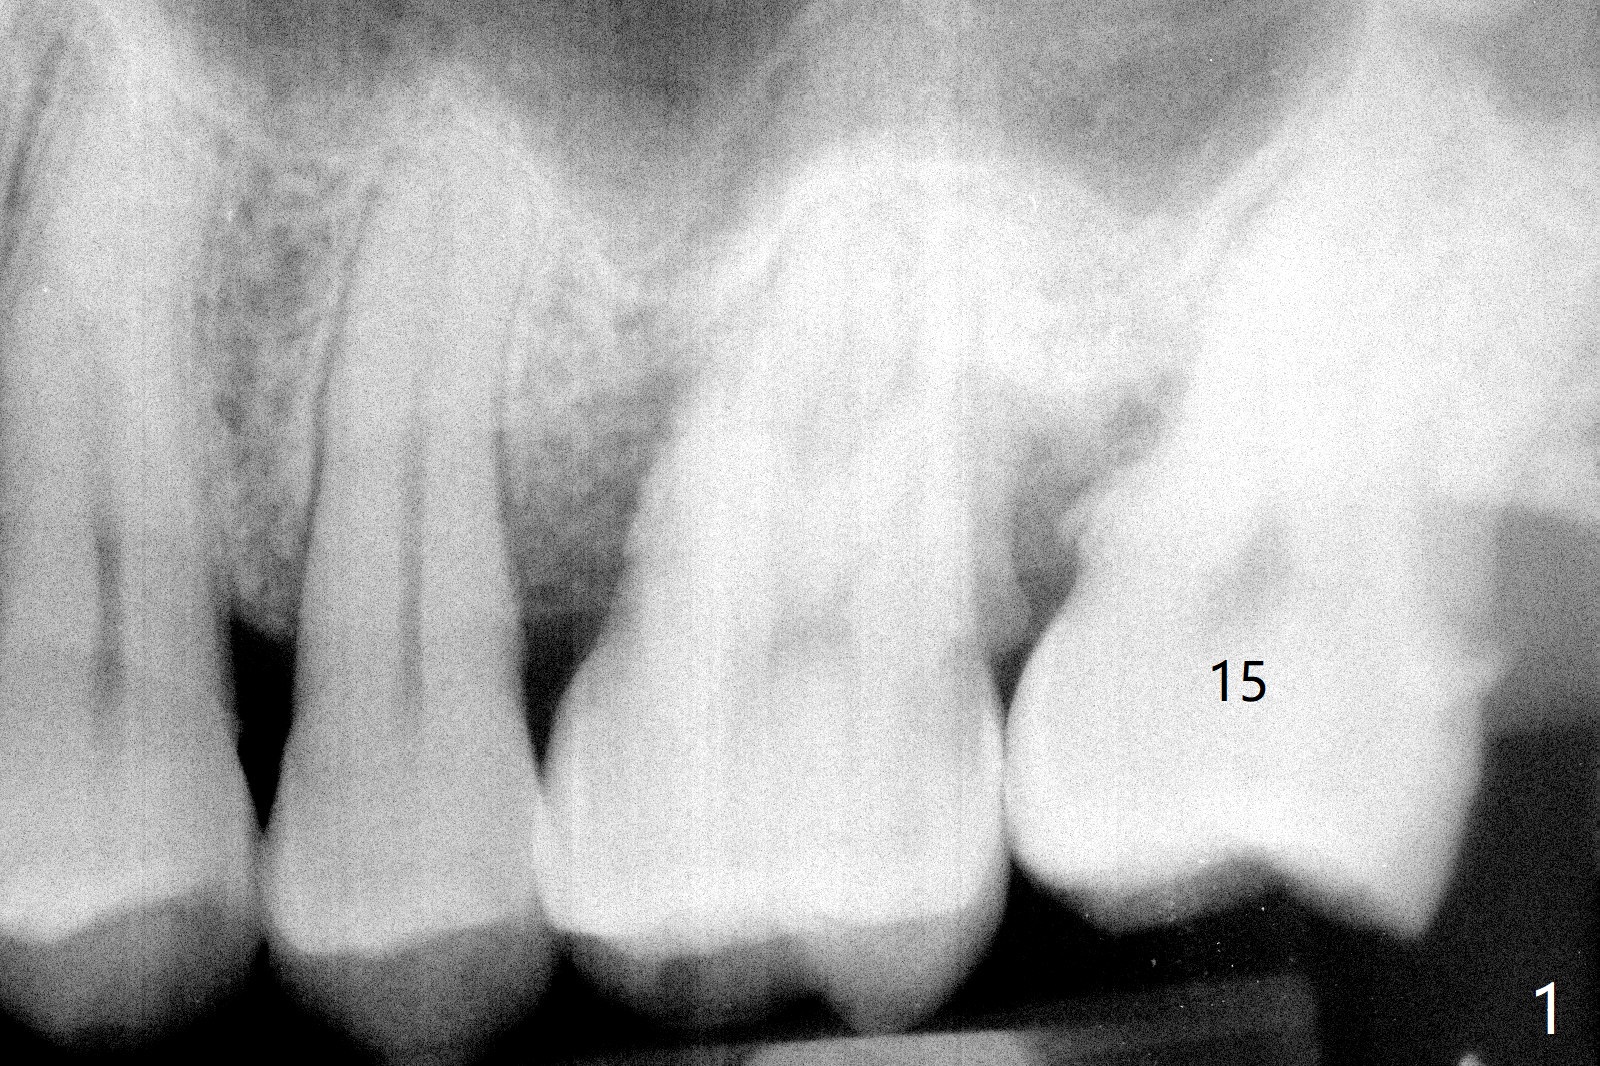

72岁男4.5前左上第二磨牙位置正常(图一),当时左下第二磨牙龋齿严重(图二),后来在别的诊所拔除,最近回来要求左上第一磨牙(图三)和左下第二磨牙种植(图四),由于左上第二磨牙延申(图五),为了左下第二磨牙导板种植,左上第二磨牙近中舌侧牙尖必须磨除不少(图三:*),总之,第二磨牙导板延期种植吃力,下午第二磨牙导板即种就没有这方面困难。